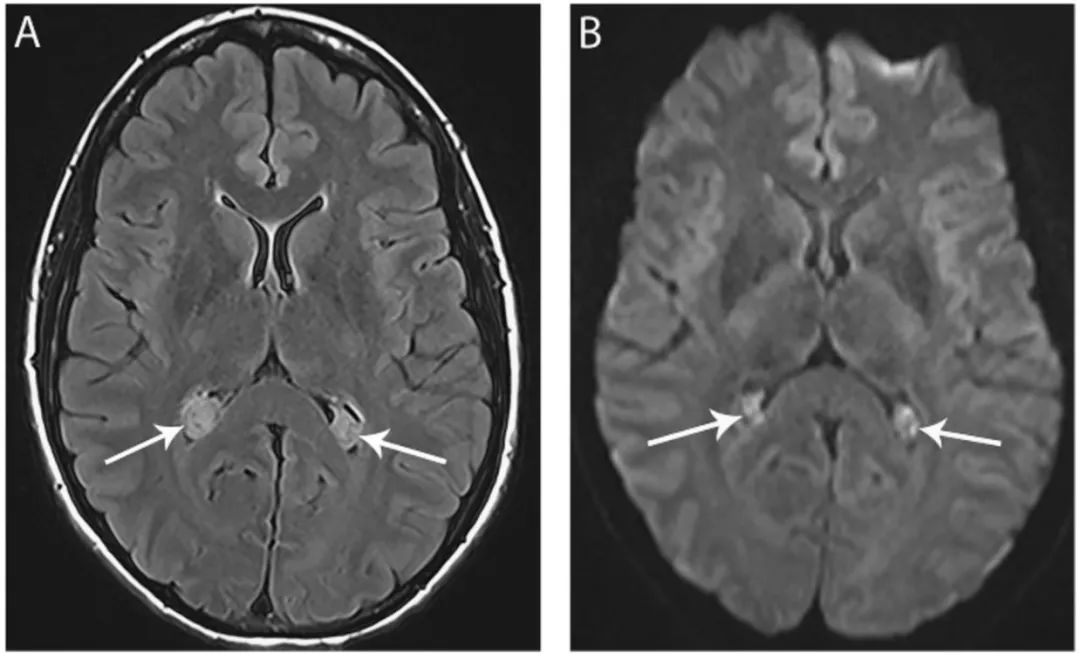

图8 脉络丛囊肿

FLAIR像(A)和DWI像(B)显示双侧脑室内脉络丛囊肿(箭头),并在DWI像上表现为特征性的高信号。